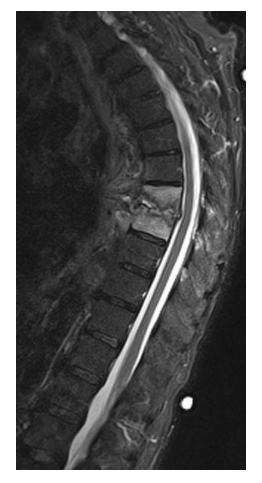

A 54-year-old renal transplant patient presents with back pain, fever, and a new thoracic kyphotic deformity. She is otherwise neurologicallyintact on examination. T2WMRIis shown.

Which one of the following is most likely?

c. Pyogenic vertebral osteomyelitis

Pyogenic vertebral osteomyelitis accounts for

2-7% of all osteomyelitis, and at-risk groups

include the elderly, diabetics, AIDS, IV drug

abusers, and the immunosuppressed. The most

common method for bacteria to spread to the

spine is by the hematogenous route. Common

sources of infection include infected catheters,

urinary tract infection, dental caries, IV drug

use, and skin infections. The next most common

route is local extension from an adjacent soft tissue infection or paravertebral abscess, followed

by direct inoculation via trauma, puncture, or following spine surgery. The nucleus pulposus is relatively avascular, providing little or no immune

response, and thus is rapidly destroyed by bacterial enzymes. The disc is nearly always involved in pyogenic vertebral infections, unlike in tuberculous spondylitis (granulomatous). The most consistent symptom is back or neck pain, fever,

neurologic deficits, radicular pain, weight loss,

and kyphosis. The spinal areas affected in descending order are lumbar, thoracic, and cervical.

Staphylococcus aureus is the most common organism and has been identified in over 50% of cases. However, gram-negative organisms (Escherichia coli, Pseudomonas spp., Proteus spp.) are associated with spinal infections following genitourinary infections or procedures. Intravenous drug abusers have a high incidence of Pseudomonas infections. Anaerobic infections are common in diabetics and following penetrating trauma. Investigations should include FBC, CRP, ESR, and blood cultures. Vertebral body and adjacent discs appear hypointense on T1-weighted and hyperintense on T2 weighted MRI, and both

enhance on T1 + contrast imaging. Positive radiographic findings are not evident for at least

4 weeks after the onset of symptoms: the earliest

detectable finding is disc space narrowing, followed by localized osteopenia and finally destruction of the vertebral endplates. Technetium-99m bone scanning is valuable in the early diagnosis of pyogenic vertebral osteomyelitis because it demonstrates positive findings before X-ray changes.